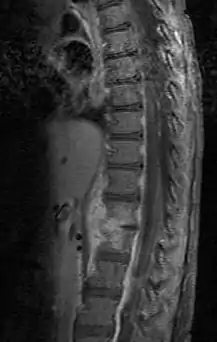

| Discitis in a 2 year old child. | |

Diagnosis is usually apparent on MRI although plain X-rays and CT examinations can be suggestive. The MRI will reveal air changes in the disc and possibly even external involvement involving the bone or epidural regions. A biopsy may be performed and helps with diagnosis in some cases but often an organism is not obtained. C-reactive protein levels and ESR levels will be elevated and are useful for treatment. Often, the white blood cell count will be normal and the patient will be afebrile.